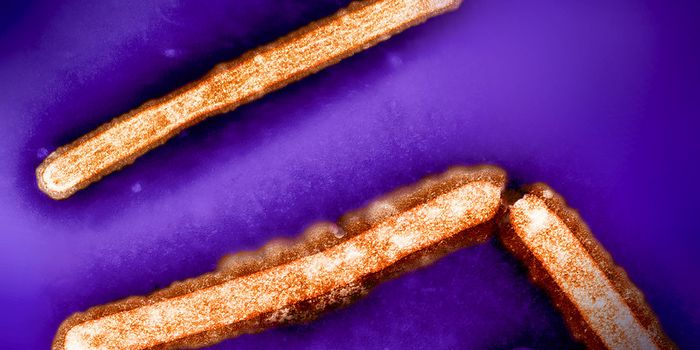

FEB 04, 2025Clinical & Molecular DXSudan virus (SUDV) can infect people to cause Sudan virus disease (SVD). Right now, an outbreak of SVD has been detected ...